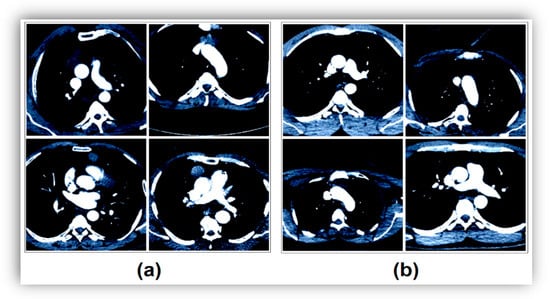

For variable-resolution images, the data clipping technique removes unnecessary regions and emphasizes the image area that should be in focus. This ensures a successful training result for training AI models. Each image in the dataset used in this study was of variable resolution, and each image was converted (cropped) to 224 × 224 resolutions in a center–midpoint format. All these operations were performed using the Python 4.0 language Torch and Numpy libraries. The image resolution of 224 × 224 was chosen because it is the same as the input resolution of the transform models. Example transform images showing this process step are shown in Figure 2. After the data cropping technique, the ROI technique was applied to each image using the Python language, and the sample image set obtained is shown in Figure 3.

The first step is to refine the dataset to make it more useful before training the transform models. For each image, the Python code ’ResizedCrop(224)’ was used to reconstruct the resolution from the center of the image to 224 × 224. Then, the ROI technique, supported by the Pandas and Numpy libraries and designed in Python, was applied to the images to foreground the desired regions. An example image subset of this step is shown in Figure 2 and Figure 3.

Figure 3. Application of the ROI technique after data cropping: (a) CT images without thymoma disease, and (b) CT images with thymoma disease.